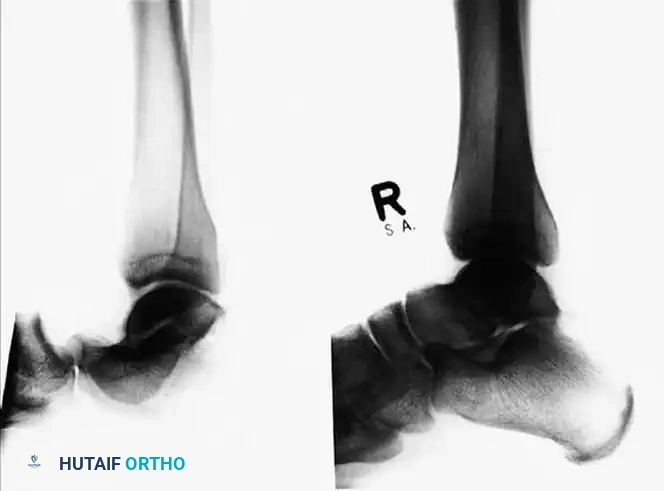

After closed reduction of the dislocation, no fracture is apparent on the standard lateral radiograph.

CT scans of the same patient, however, clearly demonstrate an intraarticular talar fracture requiring fixation.

Radiographic appearance after open reduction and internal fixation of the identified talar fracture.